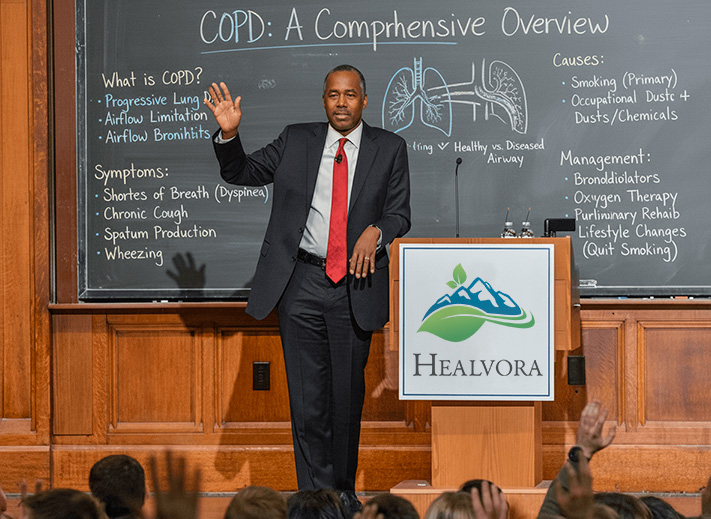

Pulmonologist Exposes the Hidden Mucus Layer That's Suffocating 87% of COPD Patients (And Why Most Treatments Can't Reach It)

There's a hidden problem affecting 87% of COPD patients right now.

I'm talking about what respiratory researchers now call "the suffocation layer"-but patients describe it more simply: the mucus trap.

Your Mucinex Can't Reach What's Actually Choking You